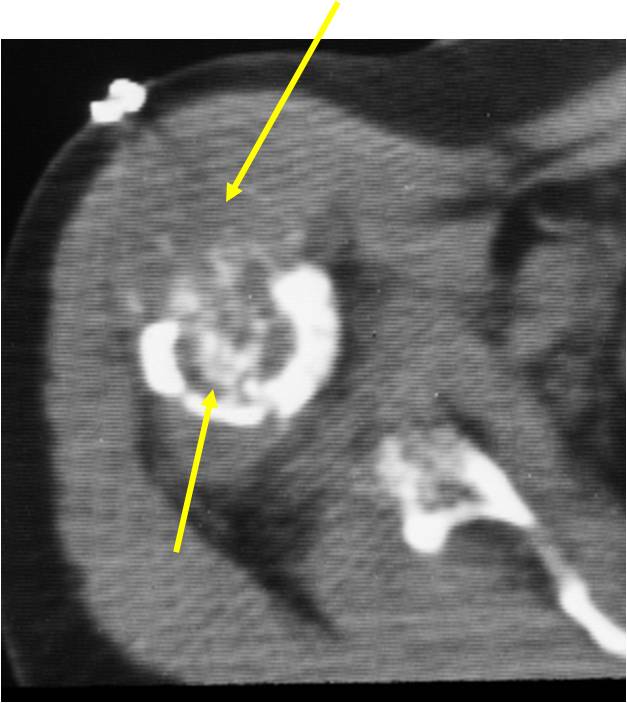

Radiology emulates pathology: Biphasic Tumor

- One region low grade chondrosarcoma

- Second more aggressive area with bone destruction, lysis of calcification, soft tissue mass

- Cortical permeation and a soft tissue mass in 70% of cases

Ill-defined, lytic intraosseous lesion

- Or extraosseous soft tissue mass

- Devoid of calcifications in continuity with lesions having the features of a cartilaginous tumor

Characteristically abrupt transition between chondroid tumor and dedifferentiated, lytic component

Bone may be expanded and adjacent cortex thickened

(Right Arrow)Aggressive Lytic Area (Dedifferentiated Sarcomatous Component) Cortical Destruction Soft Tissue Mass without Calcification